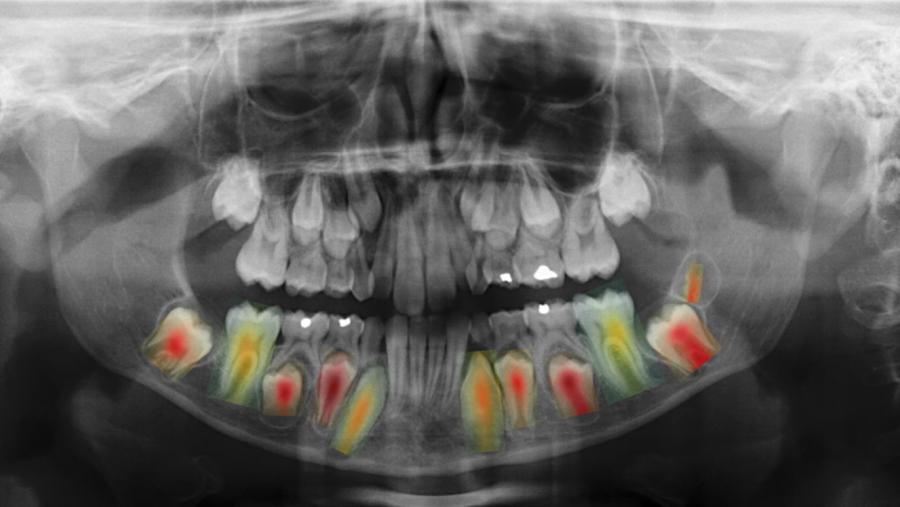

“O primeiro foi desenvolver unha metodoloxía para estimar a idade e o sexo a partir da radiografía completa, un paso preliminar que nos permitiu acadar unha precisión superior á dos métodos existentes”, explica Nicolás Vila. “Empregamos métodos baseados en mapas de calor para determinar as rexións da radiografía máis relevantes cando tratamos de estimar a idade”, prosigue o autor da tese. “Deste xeito, confirmamos o coñecemento adquirido nos estudos clínicos previos, que afirmaban que a rexión dental é a que máis inflúe na predición final”, afirma o investigador posdoutoral. O traballo, dirixido polas científicas María José Carreira e Inmaculada Tomás, contou tamén coa colaboración das odontólogas Paulina Varas e Ángela Aneiros.

Por último, o equipo de traballo desenvolveu unha nova metodoloxía para detectar as pezas dentais presentes na radiografía, co obxectivo de usalas no proceso de estimación. A investigadora María José Carreira explica como “tras estimar a idade e o sexo de cada dente por separado, as predicións individuais resultantes combínanse, para obter unha única estimación global”. “Grazas a esta integración temos un sistema altamente explicable, xa que en todo momento é posible saber en que dente confiar máis, e en cal menos”, destaca a investigadora do CiTIUS. Ademais, e para reforzar esta capacidade de interpretación, o sistema proporciona mapas de calor adicionais, destinados a avaliar as zonas de cada dente que máis inflúen na predición final.